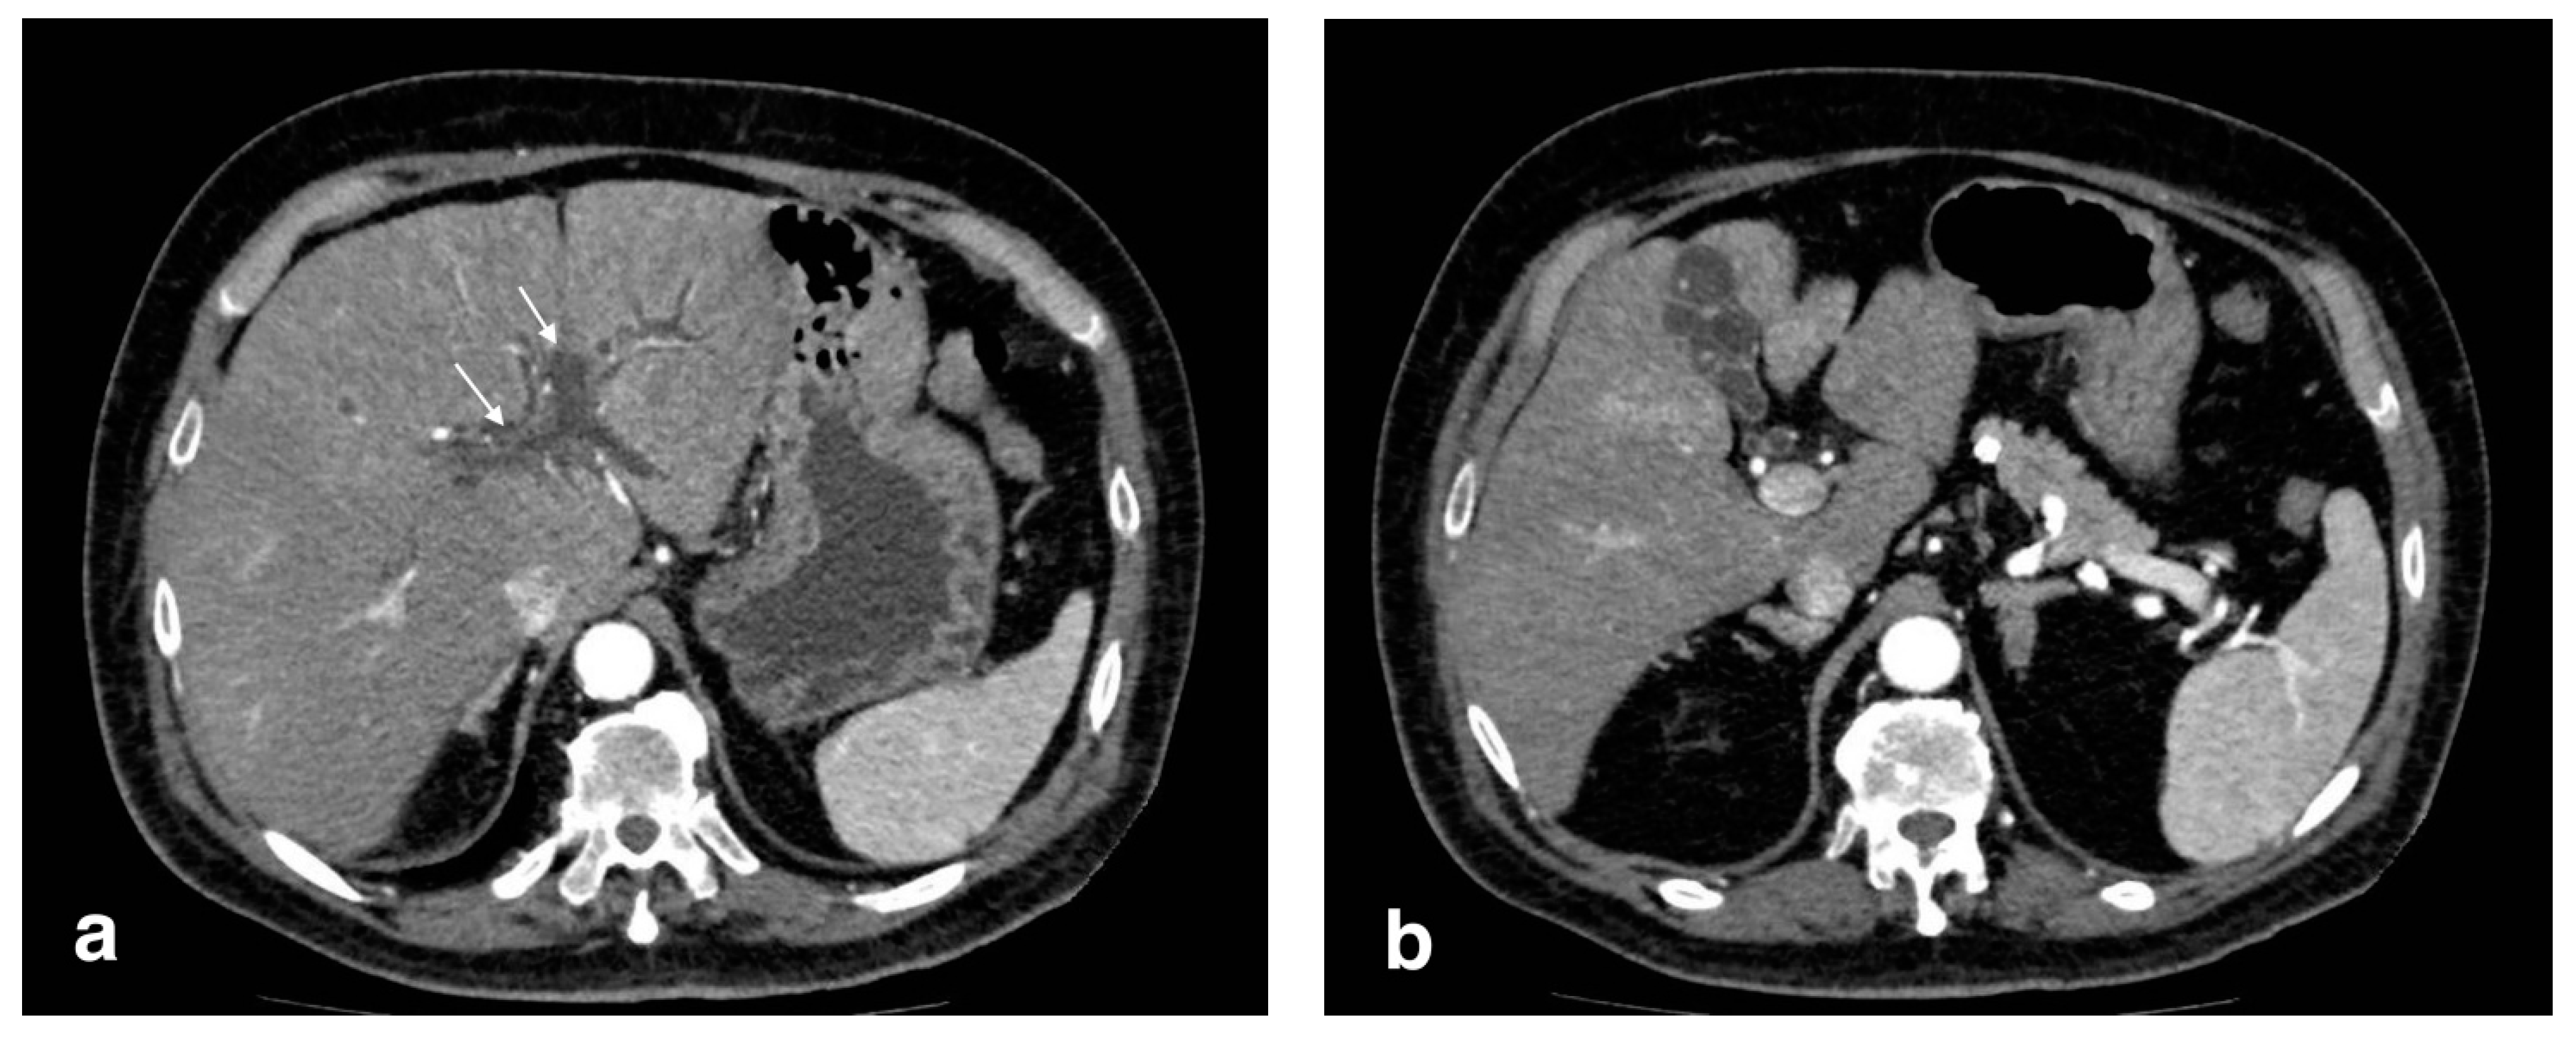

Figure 2.

Gangrenous cholecystitis: irregular wall thickening with bulging and focal defects in the gallbladder wall (black arrows, (a)). Coexisting hepatic hyperemia (arrowheads) and pericholecystic fluid (white arrows) (a,b).